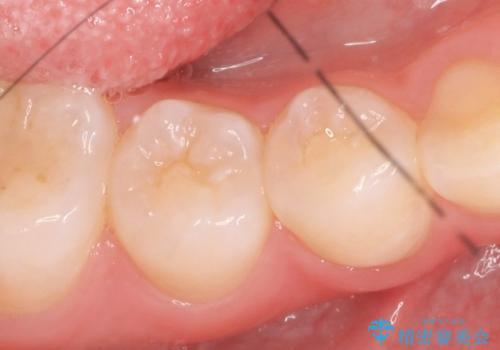

不適合なクラウンのやりかえ

セラミッククラウンによる奥歯のむし歯治療